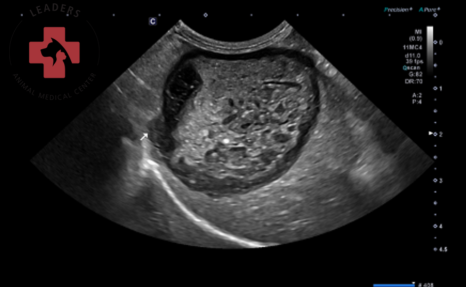

- 혈액 검사: 전신 염증 수치(CRP) 및 췌장염 수치(cPL)의 급격한 상승이 확인되었습니다.

- 복부 초음파: 담낭 내부에 유동성이 없는 다량의 점액종(슬러지)이 확인되었으며, 특히 담낭 외측벽의 구조적 이상, 담관 확장, 췌장의 부종, 담낭 주위의 복막염 등 담낭 파열을 시사하는 강력한 소견들이 관찰되었습니다.

복부초음파 검사 결과 / 출처: 24시 동탄 리더스 동물의료원